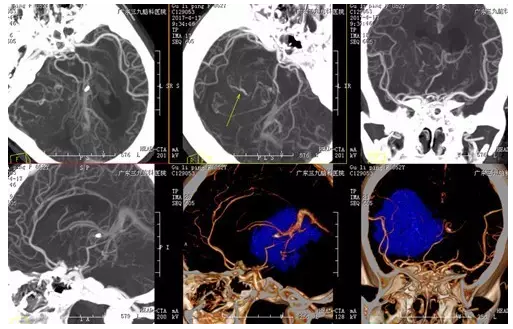

图2:术前CTA显示中后颅窝占位病变内多发血管影

中枢神经系统血管周细胞瘤的治疗以手术为首选,总体预后良好,但复发率高,手术全切可降低复发率,对手术次全切者有必要行放射治疗。中枢神经系统血管周细胞瘤血供丰富,发现时病变常体积已较大,切除时难度相对较大,本例病变体积巨大,CTA提示血供丰富,且与静脉窦关系密切,在手术中除重要神经血管的保护,还需特别注意直窦、横窦、乙状窦、大脑大静脉等重要血管的保护,术中注意止血,出血量少,未出现明确术后并发症,术后患者恢复良好。